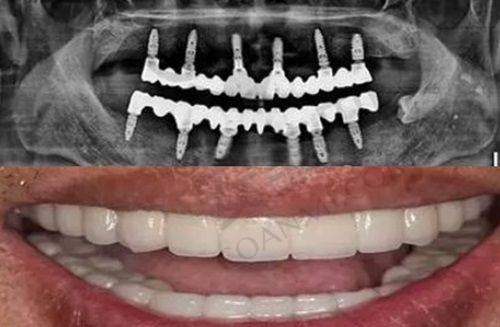

在诊疗项目上,医院下设牙齿种植、牙齿矫正、美学修复、综合治疗、儿童齿科、VIP会员六大特色诊疗。其中,“MCIC复杂病例种植”是针对半/全口长期缺牙、牙槽骨缺失、中重度牙周病等复杂疑难种植实例而设立的专项缺牙病例种植,能让更多缺牙人重拾口福。同时,医院还拥有矫牙黑科技——iTero智能口内扫描仪,1分钟扫描牙齿,3分钟取模型成功,5分钟就可预知牙齿矫正的成效,并且在矫正过程中能实时掌控矫治进度,让矫正更舒适、快捷、方便。

收费问题是大家比较关心的。重庆美奥口腔医院的收费在重庆当地偏中等。从种植牙价格来看,韩国登腾种植牙2899元起/颗(含植体 + 基台,赠送牙冠);美国皓圣种植牙4899元起/颗(含植体 + 基台,赠送牙冠);瑞典诺贝尔种植牙9999元起/颗(含植体 + 基台,赠送牙冠)。与市场价格相比,较为实惠,比如瑞典诺贝尔种植牙,一般市场价格在1.5万元左右一颗,而美奥口腔因连锁需求量大,进价低,所以给到患者的价格更便宜。